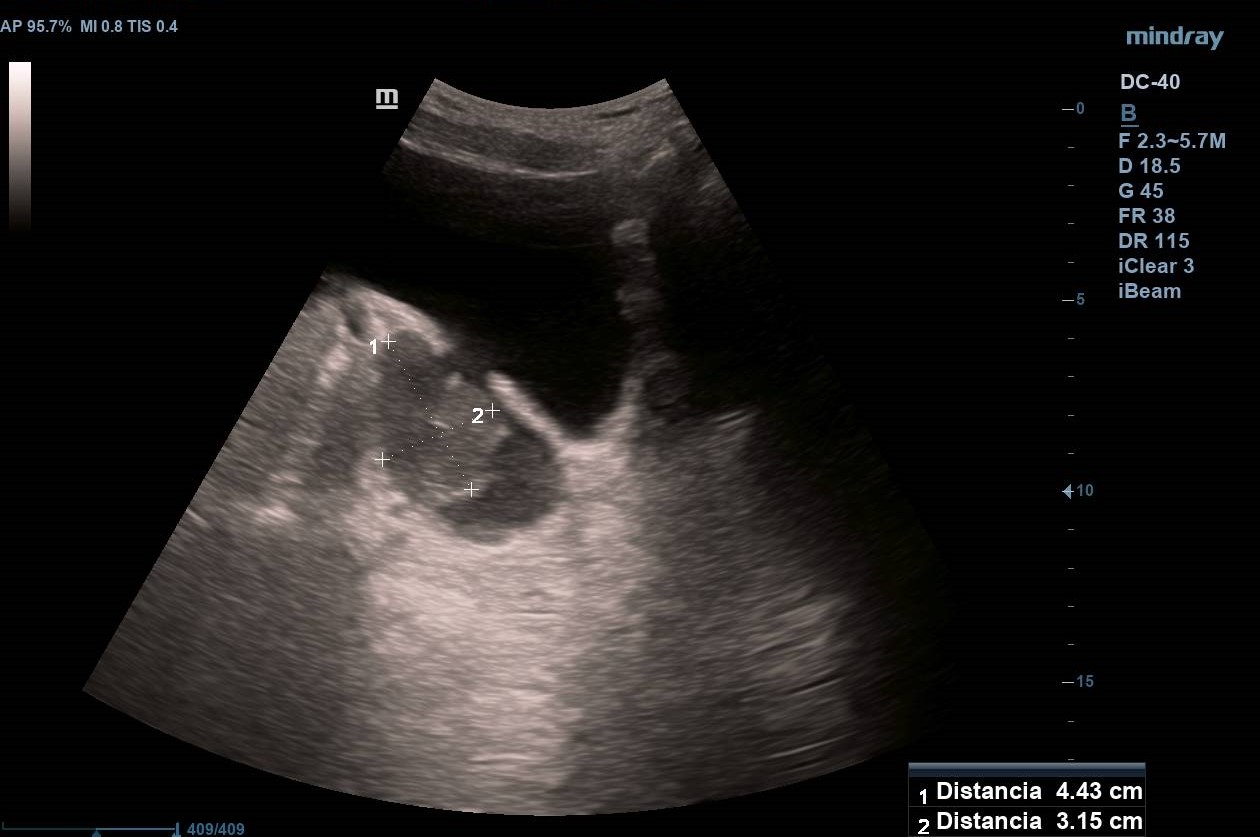

Divertículo vesical de 6 cm de diámetro en cuyo interior se observa masa homogénea de 4,43 x 3,15 cm que no capta Doppler y que parece depender de pared diverticular. Próstata homogénea de 37 cm3 (Imagen 1).

Masa vesical sospechosa de carcinoma de vejiga. Diagnóstico diferencial con coágulo vesical.